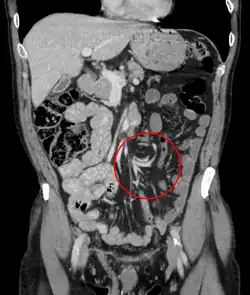

| Coronal CT of the abdomen, demonstrating a volvulus as indicated by twisting of the bowel stock | |

Coronal view of sigmoid volvulus with "whirlpool sign" -